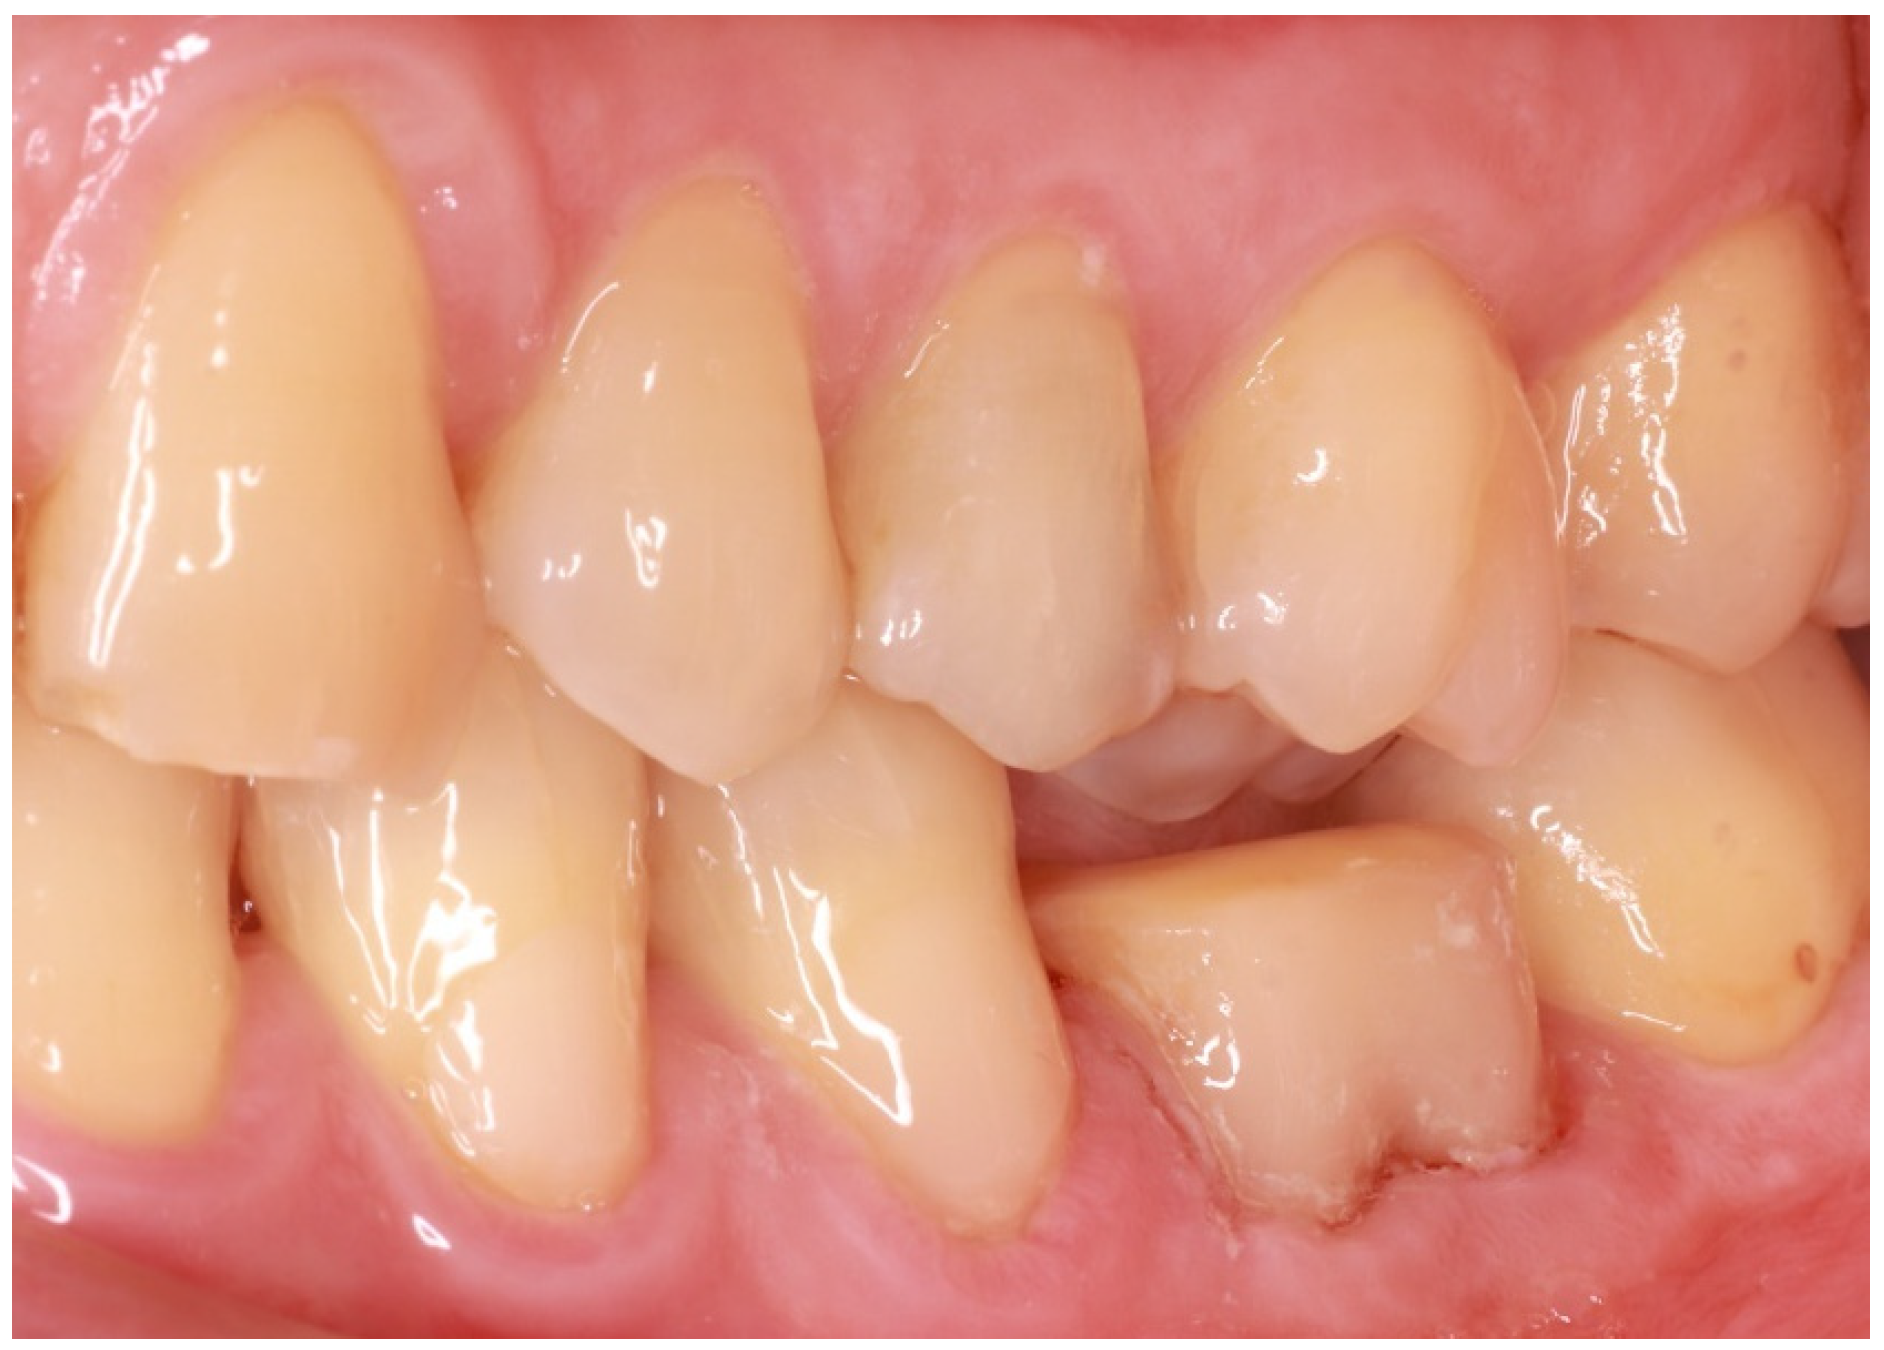

A 57-year-old male patient presented to the XXX Clinic of the XXX University of XXX seeking dental rehabilitation. The chief complaint was the compromised restoration of tooth No. #36 (Figure 1). His medical record did not reveal any disease or medication intake. Clinical examination revealed multiple immediate composite resin restorations with unacceptable morphology and adaptation to the remaining tooth structure as well as lack of contact point but rather a large, concave contact area facilitating food entrapment. After radiographic examination and given that the tooth was endodontically treated and the antagonist was slightly overerupted and limited prosthetic space would be available, the proposed treatment plan included the fabrication of an all-ceramic endocrown. Implant-supported restorations were also proposed for the restoration of missing teeth No. #46 and 47 but due to financial limitations, the patient only wished for the restoration of tooth No. #36 (Figure 1).

Figure 1. Initial situation.